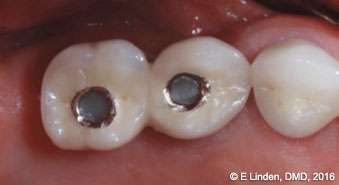

Bone sounding: Once anesthesia took effect, bone sounding was performed in order to precisely determine the bone topography (Figure 6). This step is crucial with the closed technique. The data obtained guides the clinician as to how far the laser tip needs to go into the pocket. The clinician will then move the laser tip staying 1 mm-2 mm away from the bone.

Figure 6: Preoperative bone sounding (under local anesthesia) was needed to determine the bone topography